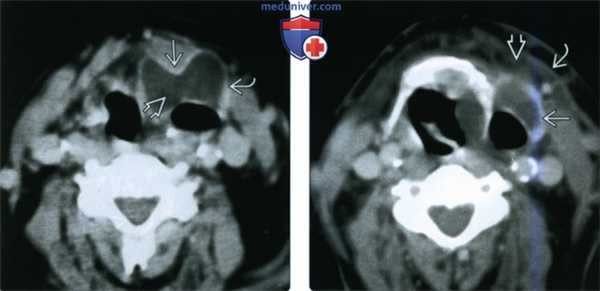

(Слева) При аксиальной КТ с КУ у пациента с клиникой лихорадки и объемного образования шеи визуализируется заполненное воздухом и жидкостью ларингоцеле, распространяющееся за пределы гортани (смешанное). Стенки образования толстые и накапливают контраст. Обратите внимание на наличие перешейка на уровне щитоподъязычной мембраны.

(Справа) При аксиальной КТ с КУ у этого же пациента наряду с утолщением и контрастным усилением стенки определяются воспалительные изменения смежной подкожной клетчатки и утолщение подкожной мышцы шеи. Это типичные признаки пиоларингоцеле.